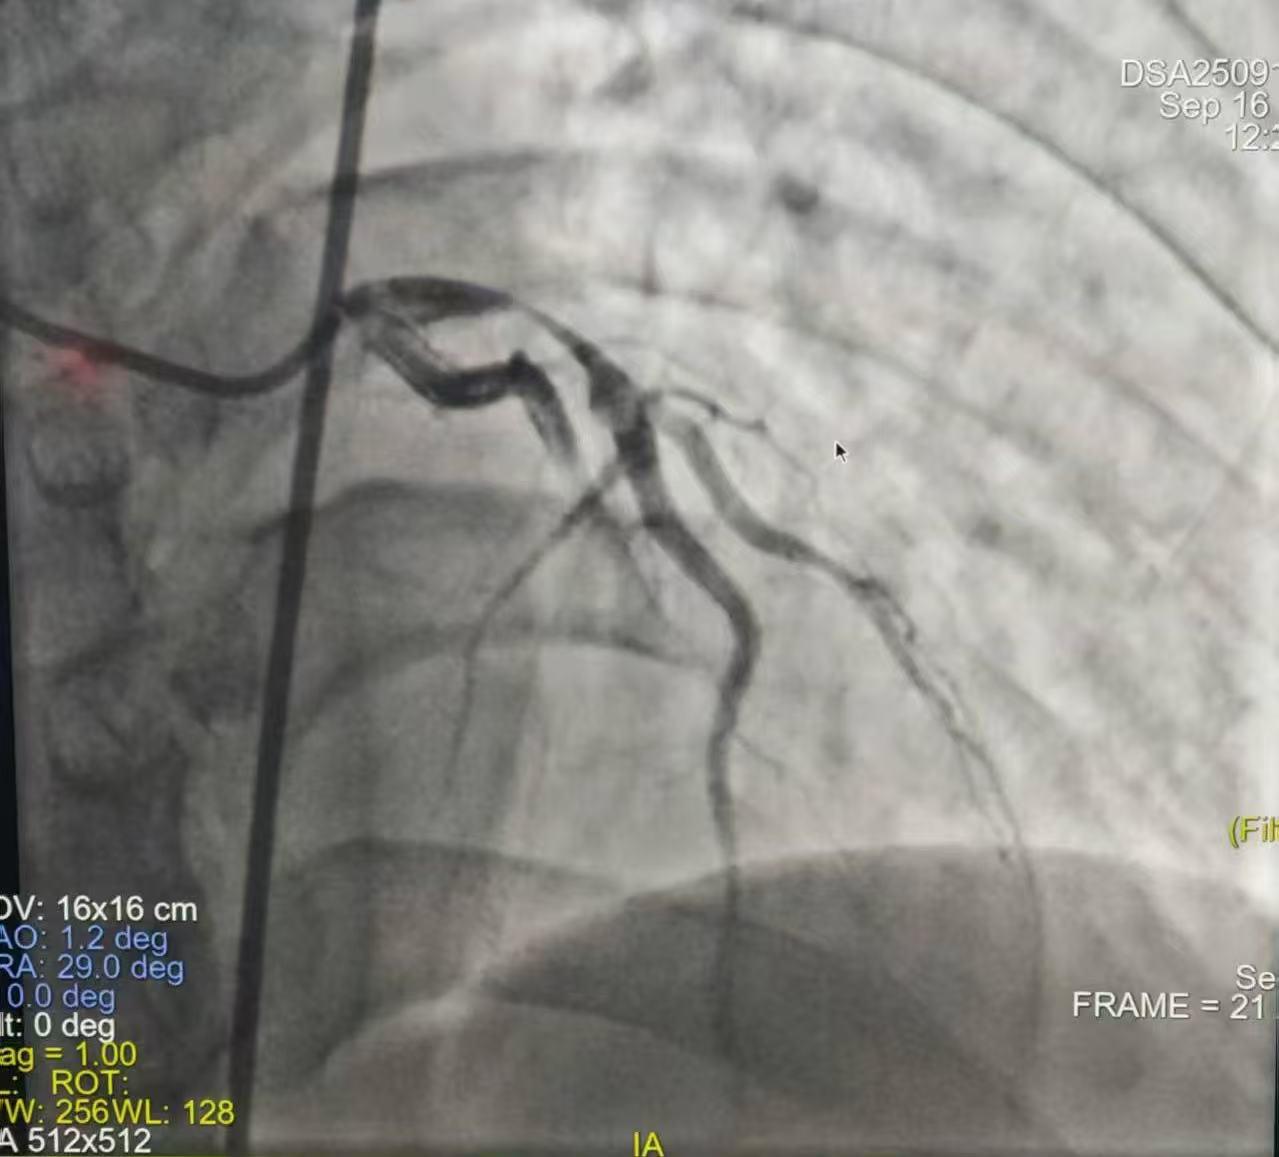

术前

就在刚转运至介入手术室时,患者突发室颤,心血管病院副院长刘云凤立即指导抢救,马玉娥医生行胸外按压、介入手术室紧急电除颤,转复窦律……经医护人员全力抢救,患者意识逐渐转清,在介入室行急诊PCI,冠脉造影提示左前降支LAD近段几乎全闭塞,顺利植入一枚支架,开通闭塞冠脉血管,实现梗死冠脉血流灌注。